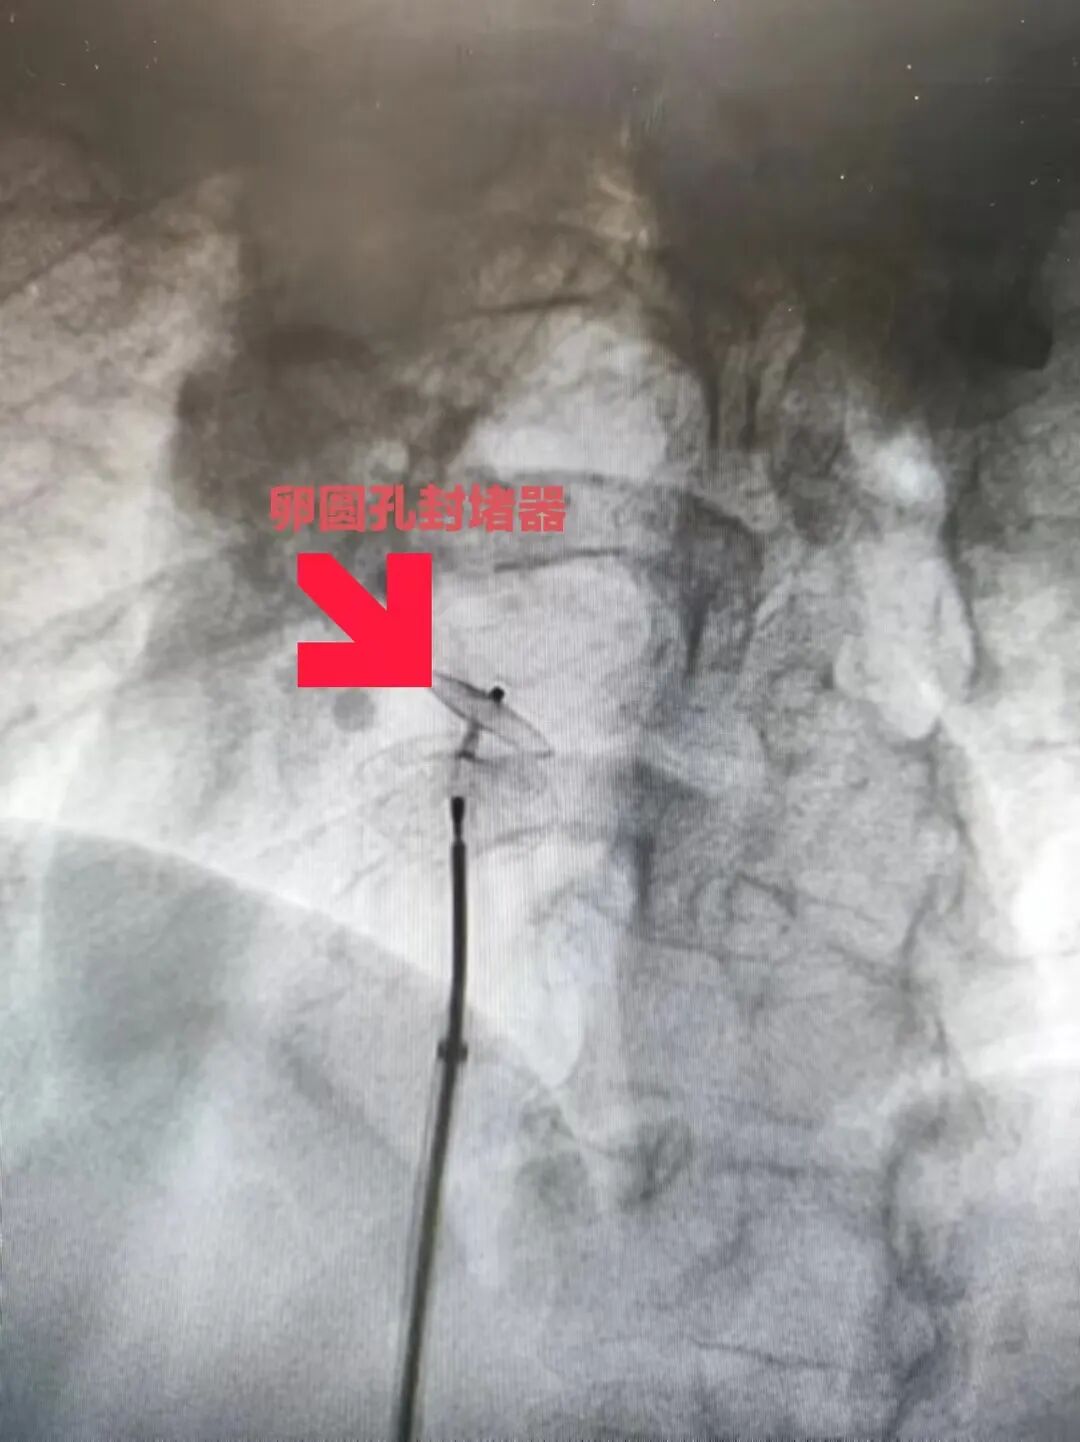

近日,在心内科执行主任毛庆的主持下,心内科团队顺利完成一例PFO封堵术+冠脉药物球囊扩张术(DCB)的一站式手术,一次手术,解决了患者的两个“心病”。 患者孙某,58岁中年女性,因“反复头晕五年余”来我院就诊。既往有高血压,糖尿病,腔隙性脑梗死病史。在神经内科门诊筛查右心声学造影,证实为卵圆孔未闭(PFO)。 卵圆孔是左右心房隔膜上的一个小孔,卵圆孔一般在婴儿出生后一年内会自行闭合,若大于3岁的幼儿卵圆孔仍不闭合称卵圆孔未闭,成人中约有25%左右的卵圆孔不能完全闭合。患有卵圆孔未闭的患者,容易导致偏头痛,短暂性脑缺血发作、不明原因的头晕、晕厥,甚至导致脑卒中。经皮介入PFO封堵术是目前治疗卵圆孔未闭的优选方法,具有安全、有效、创伤小的优点。 经过周密的手术方案设计,手术当天,毛庆主任在南京市第一医院心内科周陵主任指导下,顺利完成PFO封堵术。超声科周黎明主任术中超声证实,封堵器在位良好。但在行冠脉造影检查时,发现患者回旋支近中段有严重狭窄,毛庆和章传龙两位主任当机立断,为患者实行回旋支近中段药物球囊扩张术(DCB术)。据悉,使用DCB术治疗冠脉严重狭窄病变,可以避免患者血管内植入支架,其次服药周期大大缩短,对高出血风险患者或无法长期耐受抗血小板药物的的患者具有较大优势,目前也是介入治疗冠心病的主流方法之一。 此例患者,经过我院神经内科、心内科、超声科等多学科诊治,顺利完成PFO封堵术+冠脉DCB术,疗效确切。两项手术,一次完成,患者术中感觉良好,术后顺利恢复。 我院多学科团队将继续为溧水区人民的心血管健康保驾护航。